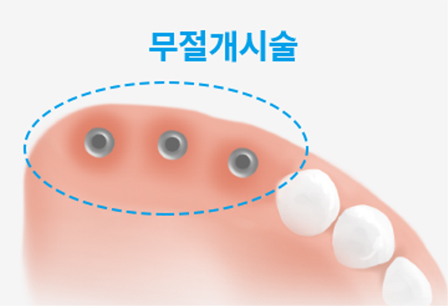

무절개 임플란트

일반적인 임플란트 수술의 경우 임플란트 픽스쳐(Fixture) 부분을 잇몸뼈에 심기 위하여 잇몸을 절개하게 됩니다. 이 과정에서 필연적인 출혈과 통증이 발생하게 됩니다. 이러한 절개 과정을 생략 혹은 최소화하여 통증 및 출혈을 줄이고, 회복기간을 줄인 치료방법입니다.

절개 임플란트 VS 무절개 임플란트

절개 임플란트

절개가 필요한 일반적인 임플란트 수술은 출혈, 붓기로 인한 통증과 불편함이 동반되고 염증과 감염이 발생할 수 있습니다.

무절개 임플란트

절개를 하지 않는 임플란트 수술은 붓기와 출혈이 적어 수술 후 통증이 거의 없고, 염증과 감염 위험이 적어 회복이 매우 빠릅니다.